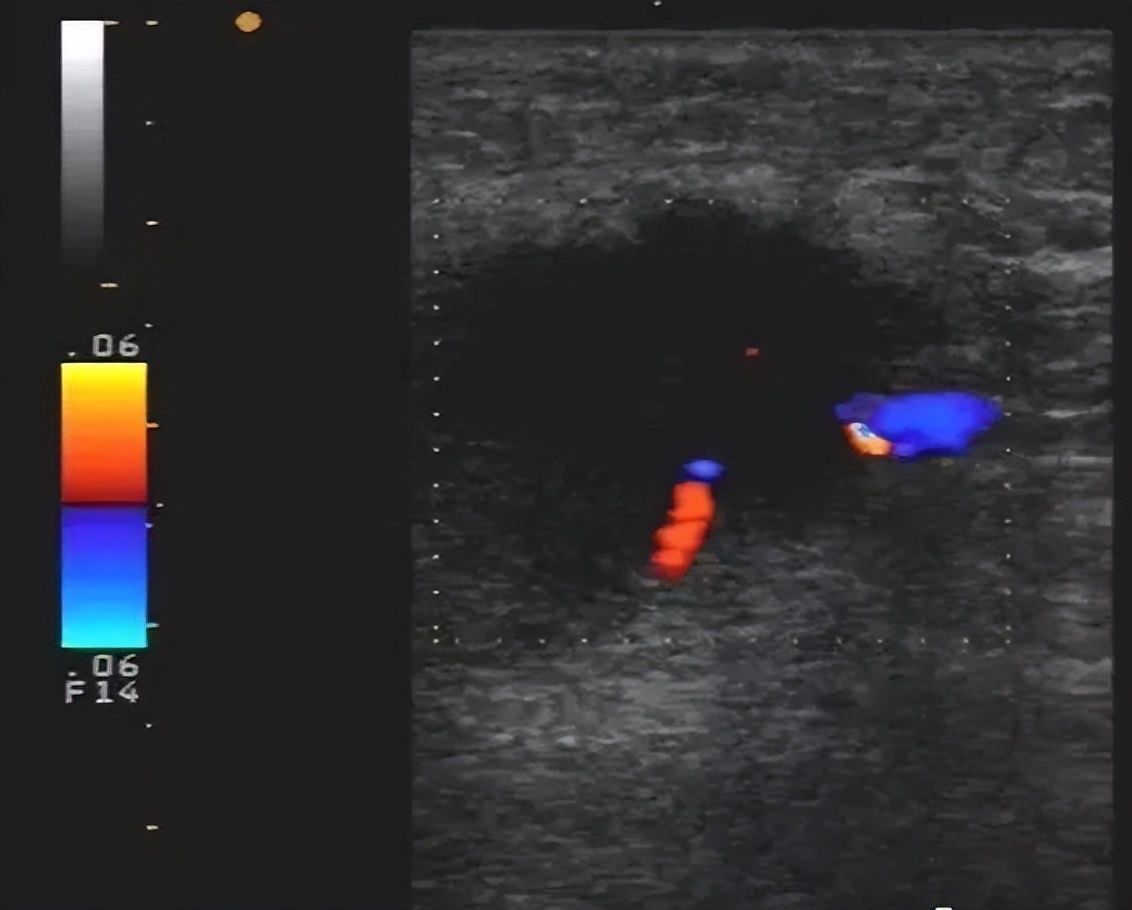

3. 副乳:发生率为1%~5% ,发生部位常见于腋窝或胸前部,多对称分布。可随着月经来潮而发生周期性的变化,妊娠期增大较明显,哺乳期可有泌乳。

超声表现:一般在表浅的皮下探及乳腺样组织,位置较表浅,呈薄片状。

小的副乳应和脂肪堆积鉴别

脂肪堆积表现为腋下皮下脂肪局部增厚,边界不清,与脂肪组织相连,按脂肪组织有规律排列;小副乳不按脂肪组织有规律排列,回声类似腺体组织回声。

副乳癌